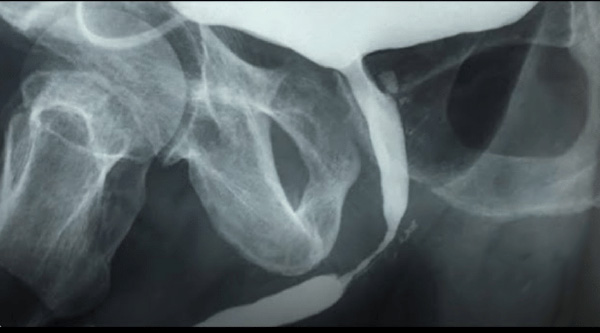

L'urètre

est le canal urinaire qui permet d'acheminer l'urine depuis la vessie vers

l'extérieur. Lorsqu'il se produit un

rétrécissement de ce canal, on parle de sténose de l'urètre. Cette